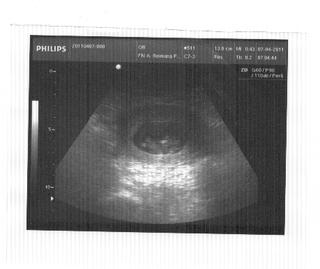

Tak ja som rano bola u Dokiho a som šťastná.Babo je v poriadku, krásne ručky, nožky, hybalo hlavičkou.....pristihla som sa že civim na monitor s vypleštenými očami a otvorenou pusou 😀 Super pocit 🙂 Najbližšia poradna 10.5. už sa nemožem dočkať 🙂 Prajem pekný dnik aj ked mi tu v PP mame kosu 😒